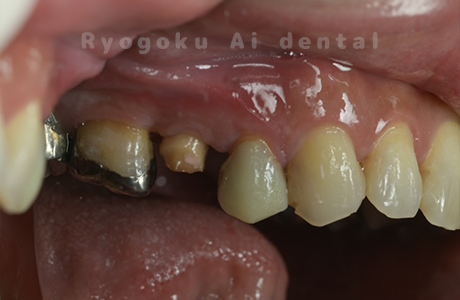

Case08

- 重度カリエス

- 治療日数

- 約半年

- 治療内容

- クラウンレングスニング、根管治療、ジルコニアクラウン

- 治療費用

- 約1,200,000円

前歯が動くとのことでご来院された患者様です。虫歯が大きく保存困難な状態でしたが、ご本人様と十分話し合い、抜歯を行わず、手術をすることで歯を抜かず保存しました。